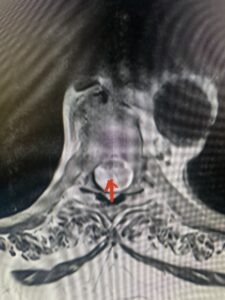

Fig. 2a Sagittal T2-weighted cervical MRI demonstrating large C4-5 herniated disc with spinal cord compression (red arrow)

Fig: 2b Axial T2-weighted cervical MRI demonstrating spinal cord compression from C4-5 herniated disc (red arrow)

This 47-year-old male who four months prior was lifting weights developed sharp pain in his neck. After that he developed progressive numbness in his arms, neck pain and headache. He said that the right arm was worse than the left. On examination the patient had long tract weakness on the right side which included his triceps, finger extensors, hip flexors, and dorsiflexors. The patient did not have hyperreflexia. MRI (Fig. 2) demonstrated a massive, extruded disc herniation with severe cord compression. The patient because of progressive myelopathy and spinal cord compression was indicated for anterior cervical discectomy and fusion at C4-5 (Fig. 3). Patient had significant improvement of weakness and numbness post operatively.